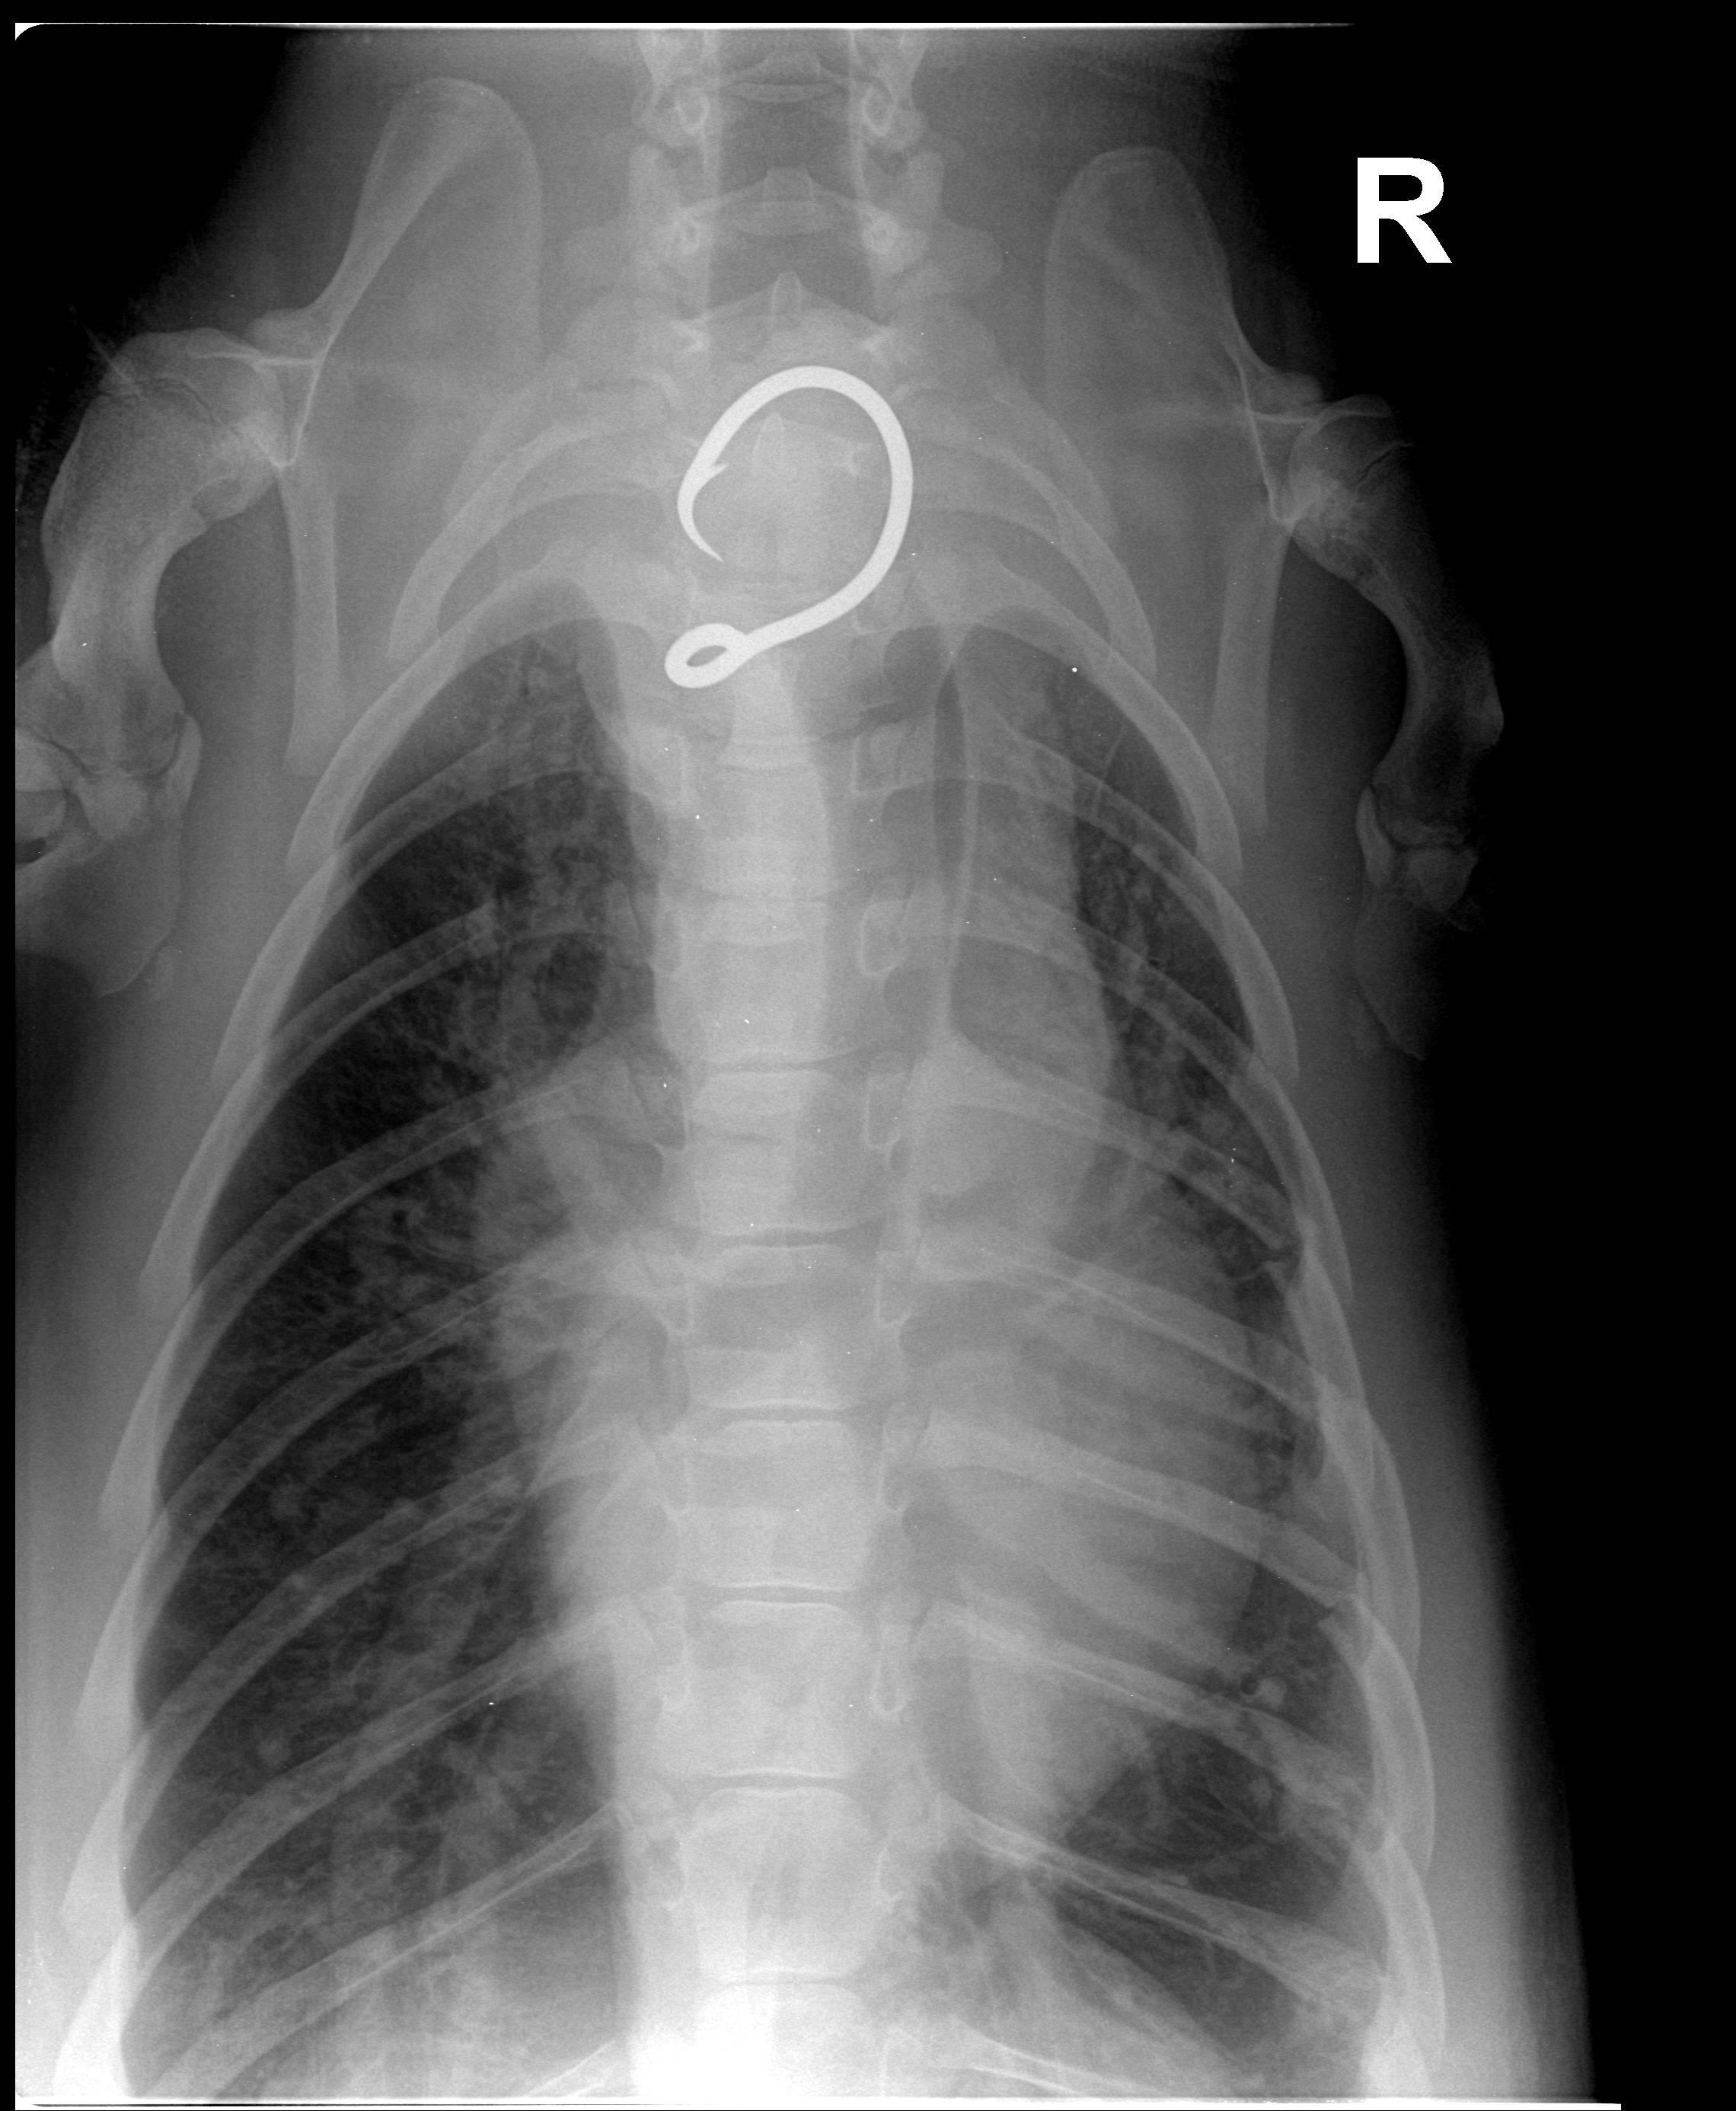

HONOLULU — The Department of Land and Natural Resources (DLNR) and the National Oceanic and Atmospheric Administration (NOAA) this morning reported that a juvenile monk seal flown by the U.S. Coast Guard from Hawai‘i Island to O‘ahu last Friday for medical treatment has died. A necropsy conducted by NOAA Fisheries revealed that the young male seal, known by his ID tags as RK68, suffered fractured ribs earlier in life, but ingestion of a fishing hook more recently is believed to be the cause of death.

Results of the necropsy reveal that the seal may have been hooked for several weeks or months. Officials believe had they received a detailed report of the hooking incident when it occurred, the chances of a life-saving response could have been much greater.